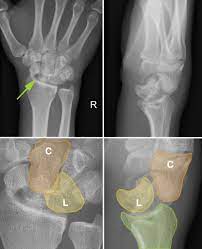

The image shows dorsal dislocation of the capitate which should be congruous with the cup of the lunate.

## Perilunate Dislocations and Fracture-Dislocations The lunate, which is normally securely attached to the distal radius by ligamentous attachments, is commonly referred to as the “carpal keystone.” ## Greater Arc Injury Greater arc injury passes through the scaphoid, capitate, triquetrum, or distal radial styloid and often results in transscaphoid, transcapitate, or transradial styloid perilunate fracture-dislocations.  ## Lesser Arc Injury Lesser arc injury follows a curved path around the lunate, involving only the capsuloligamentous tissues through the scapholunate ligament, midcarpal joint, and lunotriquetral ligaments and results in perilunate and lunate dislocations. The most common injury is transscaphoid perilunate fracture-dislocation. Disruption of the normal kinematics and stability of the carpal row lead to acute failure with a predictable pattern of posttraumatic changes.  ## Mechanism of Injury Perilunate injuries: Axial load is applied to the thenar eminence, forcing the wrist into extension. Injury progresses through several stages (Mayfield progression): It usually begins radially through the body of scaphoid (fracture) or through scapholunate interval (dissociation), although both are possible in the same injury (rare). Force is then transmitted ulnarly through the space of Poirier (between the lunate and capitate). Subsequently, force transmission disrupts the lunotriquetral articulation. This results in dorsal dislocation of the capitate and rest of the carpus relative to the lunate. Finally, the lunate can dislocate volarly out of the lunate fossa of the distal radius, in which case it is called the lunate dislocation. In a lunate dislocation, the proximal part of the capitate sits in the lunate fossa. ## Clinical Evaluation Scapholunate or perilunate injuries typically cause tenderness just distal to Lister tubercle. Swelling is generalized about the wrist with variable dorsal prominence of the entire carpus in cases of dorsal perilunate dislocations. ## Radiographic Evaluation PA, lateral, and oblique views should be obtained to confirm the diagnosis and rule out associated injuries. A CT scan may be useful in further defining the injury pattern. * **PA View** The dislocated lunate appears to be wedge-shaped and more triangular, with an elongated volar lip. Loss of normal carpal colinear “Gilula lines” and abnormal widening of the scapholunate interval >3 mm are noted. Look for associated fractures, such as “transscaphoid” injuries.  * **Lateral View** Most important view. Carefully look at the outline of the capitate and lunate. The “spilled teacup sign” occurs with volar dislocation of the lunate. A clenched-fist PA view obtained after closed reduction of the midcarpal joint is useful for checking residual scapholunate or lunotriquetral dissociation as well as fractures.  ## Classification (Mayfield) | Stage | Description | | :------ | :----------------------------------------------------------------------------------------------------------------------------------------------------------------------------------------------------------------------- | | Stage I | Disruption of the scapholunate joint: The radioscapholunate and interosseous scapholunate ligaments are disrupted. | | Stage II | Disruption of the midcarpal (capitolunate) joint: The radioscaphocapitate ligament is disrupted. | | Stage III | Disruption of the lunotriquetral joint: The distal limb of the radiolunotriquetral ligament and the ulnotriquetrocapitate complex is disrupted. | | Stage IV | Disruption of the radiolunate joint: The dorsal radiolunotriquetral ligament is disrupted, ultimately causing volar dislocation of the lunate. | ## Treatment Closed reduction should be performed with adequate sedation. Closed reduction of lunate dislocations is frequently unsuccessful. Early surgical reconstruction is performed if swelling allows. Immediate surgery including open carpal tunnel release is needed if there are progressive signs of median nerve compromise. Most transscaphoid perilunate dislocations are best treated by open volar and dorsal reduction and repair of the injured structures. Open repair should be supplemented by pin fixation while ligaments heal. Delayed reconstruction is indicated if early intervention is not feasible. ## Complications * Median neuropathy may result from carpal tunnel compression, necessitating surgical release. * Posttraumatic arthritis may result from the initial injury or secondarily from small, retained osseous fragments and cartilage damage. * Chronic perilunate injury may result from untreated or inadequately treated dislocation or fracture-dislocation resulting in chronic pain, instability, and wrist deformity, often associated with tendon rupture or increasing nerve symptoms. * Recurrent instability may necessitate ligament reconstruction with capsular augmentation. * If recurrent instability persists, lunotriquetral fusion may be necessary, with possible concomitant ulnar shortening to tension the volar ulnocarpal ligaments.